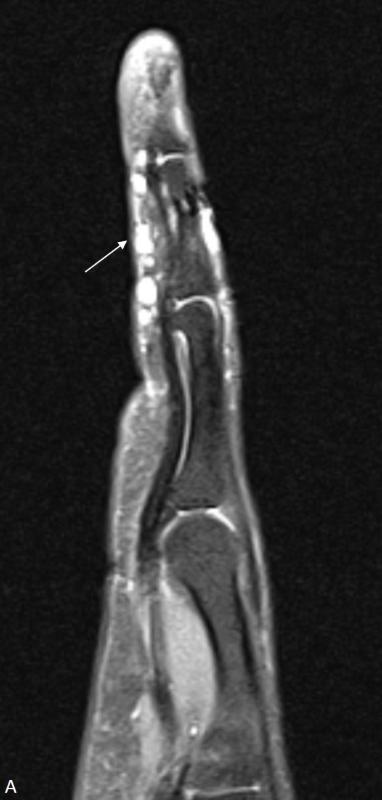

2212b132f57f8a60dd9c7f4a1305da10.jpgbe9dd1677b8ba2e94f3d512ce7329ad5.jpg

左手第4指的矢状位质子密度(PD)加权图像显示掌侧表皮下多个毫米级的结节状高信号强度病变(箭头),在T1加权图像上,这些结节表现为小的中等信号强度病变(箭头)。